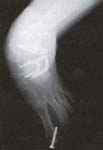

Se comparan los datos obtenidos en el preoperatorio y en el postoperatorio con una y otra técnica quirúrgica, reportando los valores medios en grados con el rango entre paréntesis para los siguiente ángulos:

- Ángulo talo-calcáneo en la proyección anteroposterior.

- Ángulo talo-calcáneo en la proyección lateral.

- Ángulo talo-primer metatarsiano en proyección anteroposterior.

- Ángulo talo-primer metatarsiano en proyección lateral.

- Ángulo calcáneo-quinto metatarsiano en proyección anteroposterior.

Las siguientes tablas resumen las medianas de los valores para los diferentes ángulos en los dos grupos.

Mediciones clínicas

Realizadas a partir de los videos que se obtienen durante las consultas en la clínica de marcha, permitieron observar que todos los pies incluidos en este trabajo fueron estabilizados mediante una y otra técnica operatoria. La recuperación del arco longitudinal del pie se observó en 5 de los 7 pies intervenidos con la técnica modificada y en 2 de 7 pies sometidos a la técnica convencional.

Los resultados obtenidos en este trabajo, especialmente la medida del ángulo talo-primer metatarsiano (que evalúa indirectamente la relación talo-navicular), sugieren que el uso de un injerto estructural para restaurar la longitud de la columna externa, así como un abordaje directo sobre la articulación talo-navicular permiten una corrección más adecuada del pie.

El ángulo entre el calcáneo y el quinto metatarsiano que busca evaluar el efecto sobre el abducto del antepié que tiene el alargamiento de la columna externa fue apenas discretamente más cercano a lo normal con la técnica modificada que con la convencional.

Finalmente, los ángulos talo-calcáneo que buscan evaluar la posición del retropié (varo o valgo) aparentemente no fueron diferentes en los dos grupos lo cual se esperaba dado que las modificaciones introducidas en la nueva técnica no incluyen tratamiento alguno sobre la articulación subastragalina.